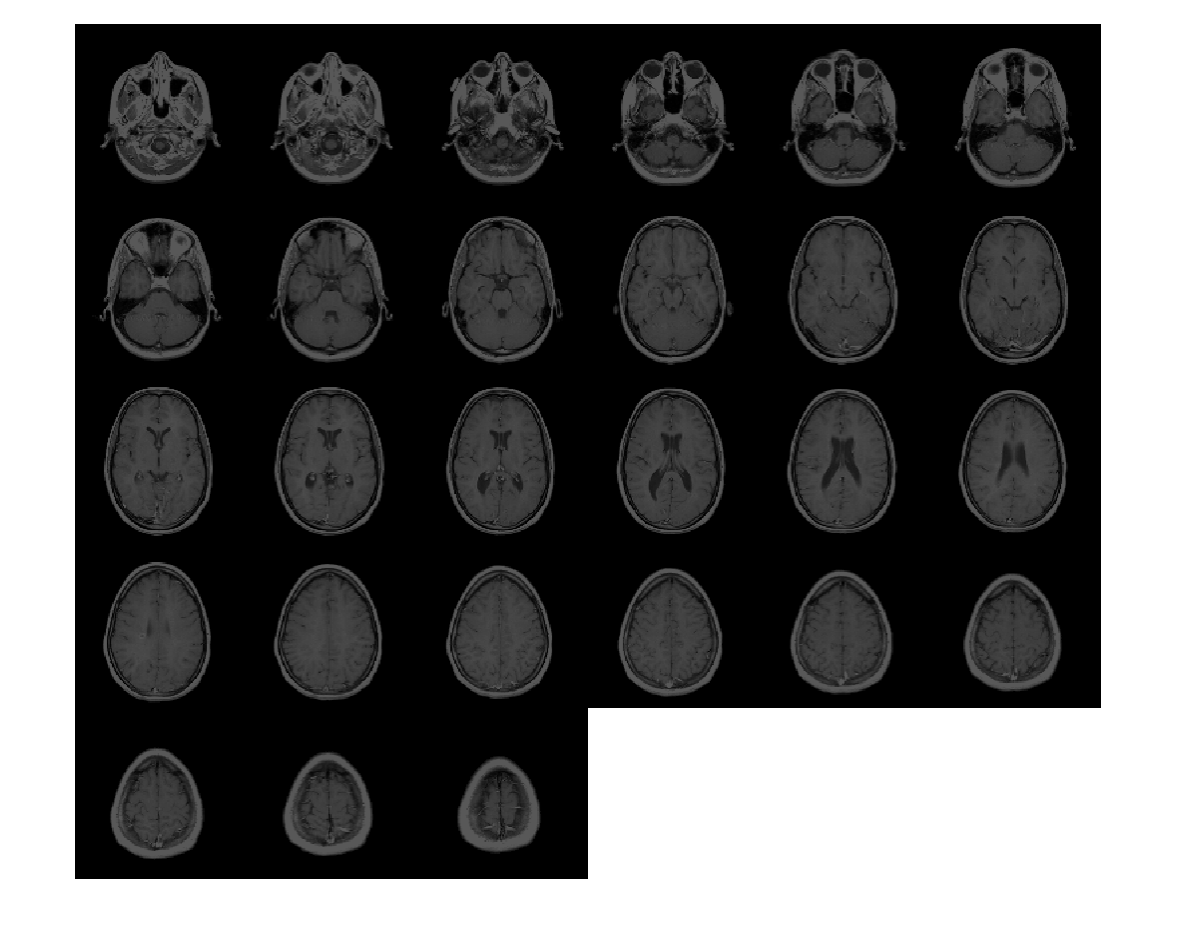

Создайте 3-D эллипсоидальный фильтр. Задайте длину полуоси 7 пикселей в y (строки) и x (столбцы) направления и длина полуоси 3 пикселей в z (плоскости) направление.

H = fspecial3('ellipsoid',[7 7 3]);

Сглаживайте объем с фильтром.

volSmooth = imfilter(mristack,H,'replicate');

Отобразите плоскости сглаживавшего объема.

montage(volSmooth,'BackgroundColor','w')

Figure contains an axes object. The axes object contains an object of type image.